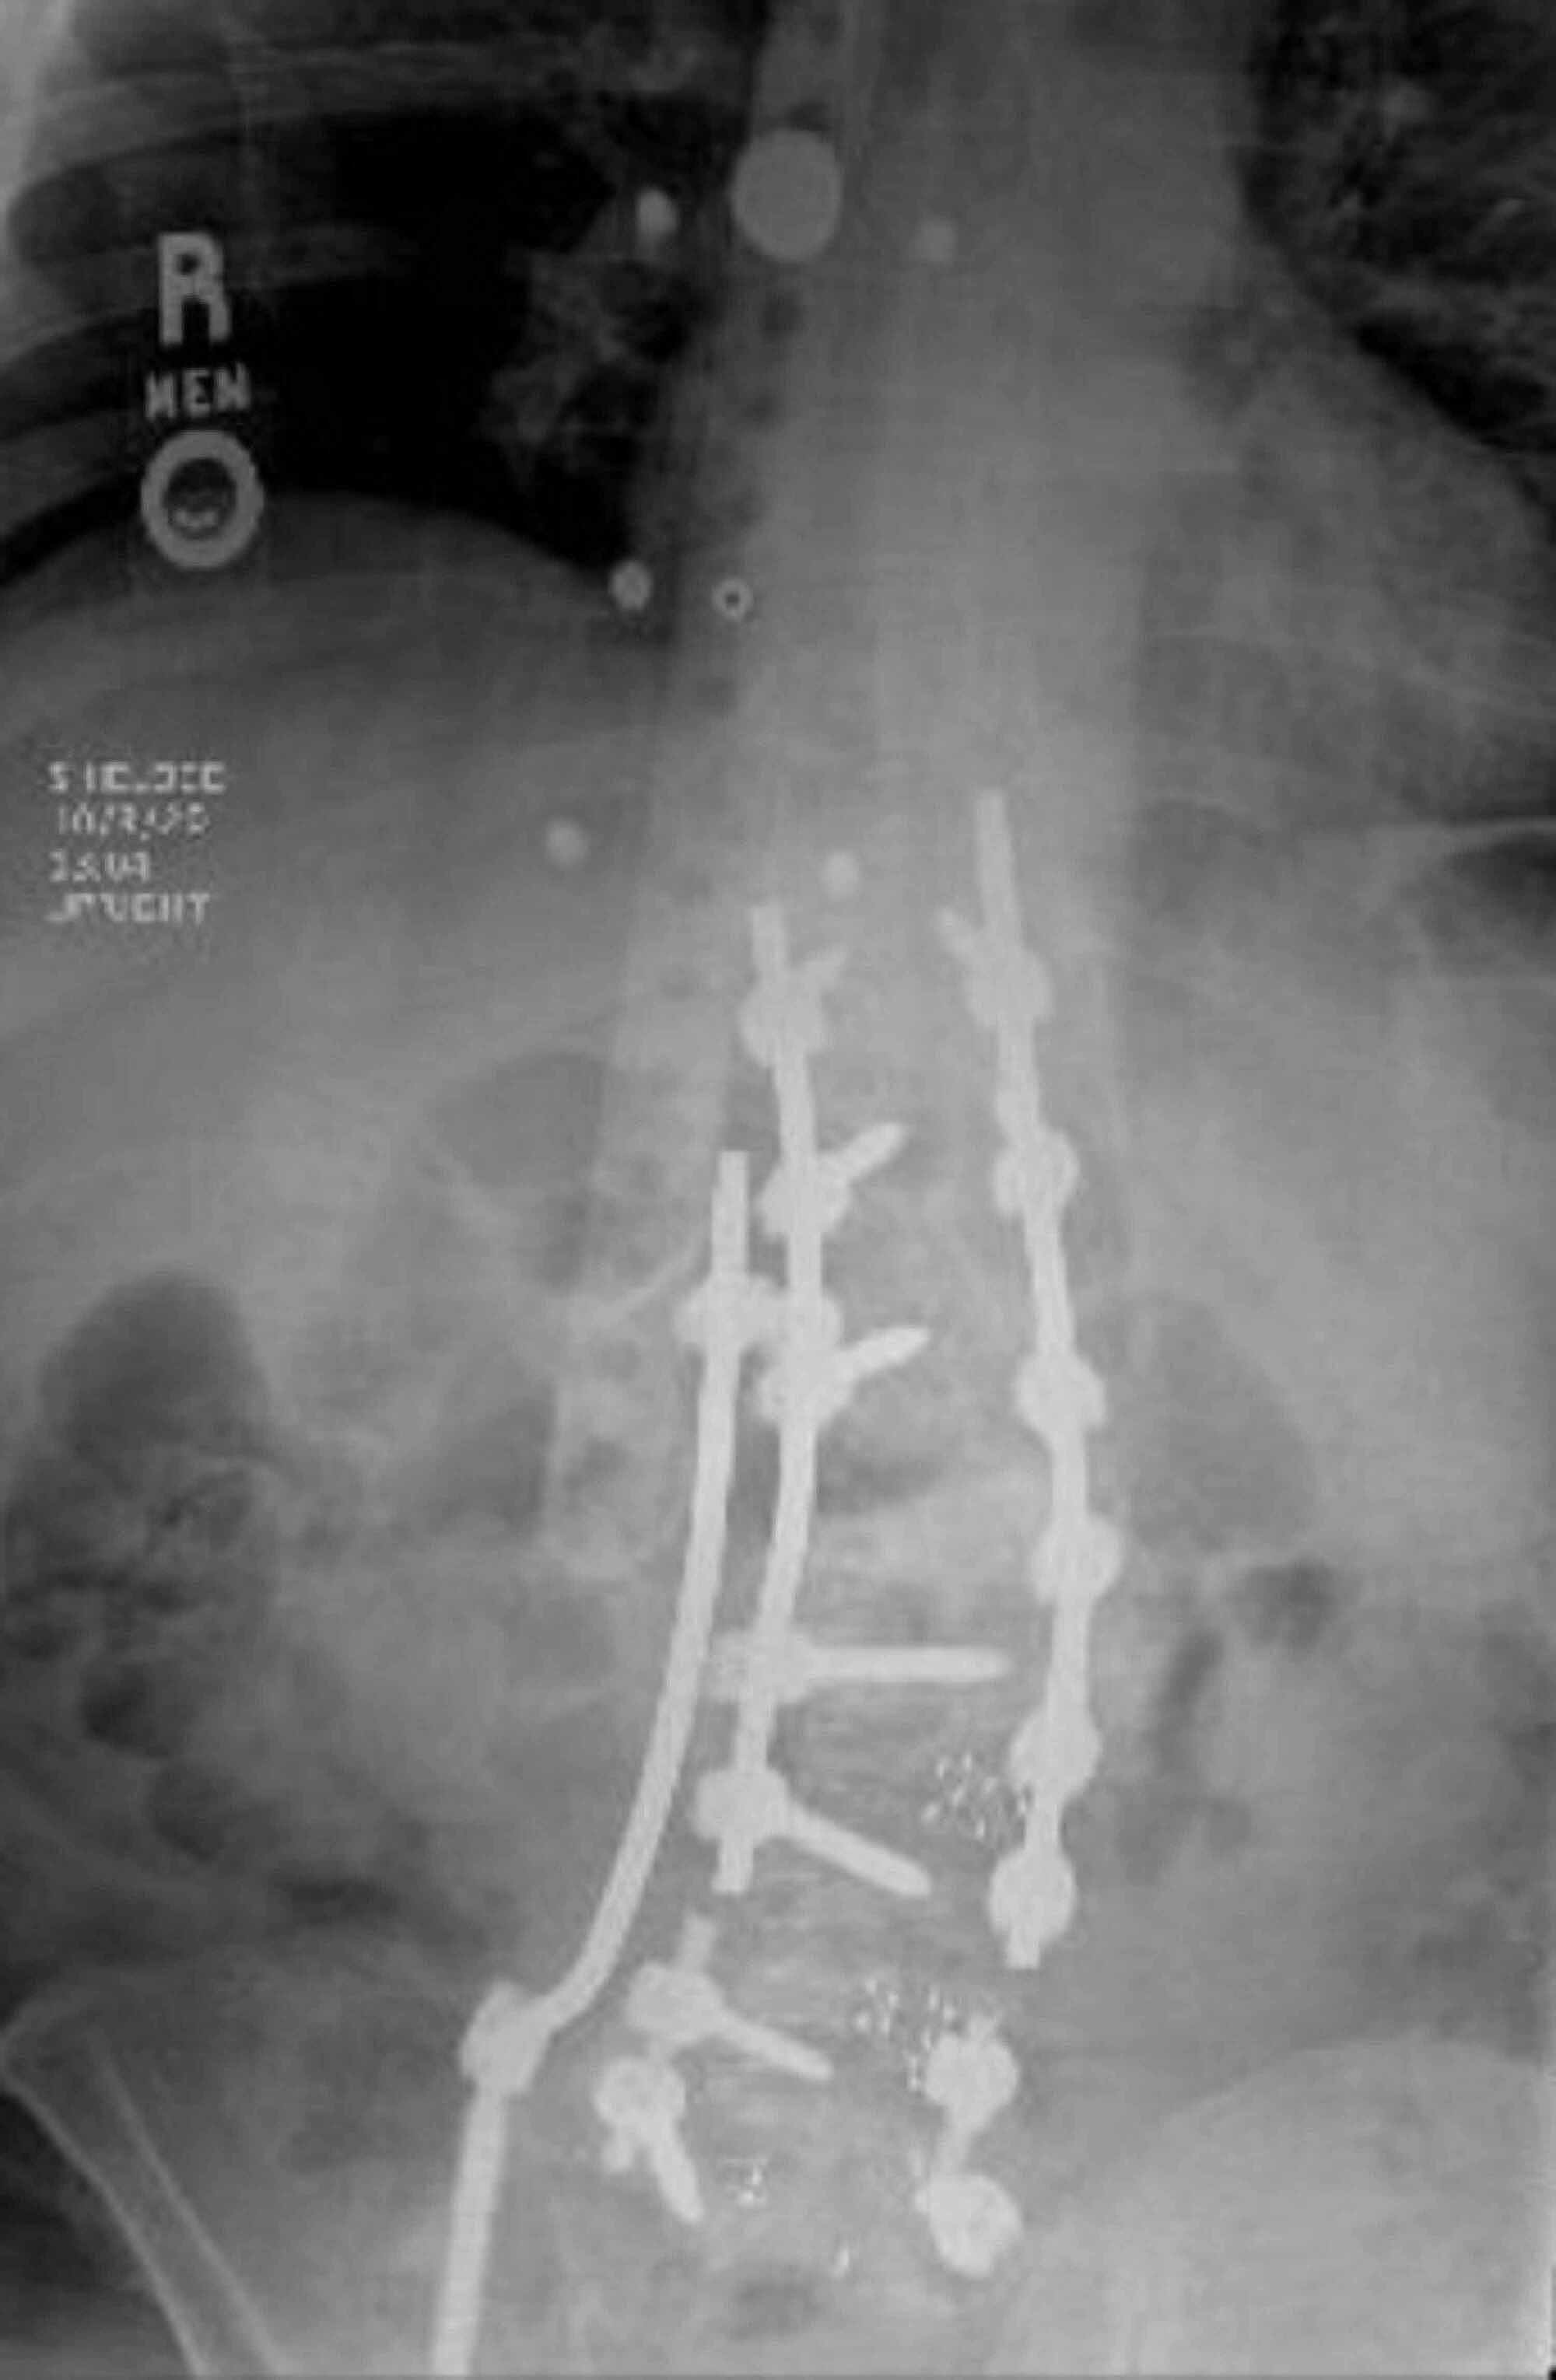

Case 4. This is a case of Type 2 CM. The kickstand rod technique Kickstand Rod The kickstand rod (kr) technique is powerful for correcting truncal shift. The kickstand rod spans the thoracolumbar junction proximally to the pelvis distally and is secured with an additional iliac screw placed. This study tested the hypothesis that the kr technique. The kickstand rod technique has been described as a novel technique for cm correction using an accessory rod on. Kickstand Rod.

Radiographs demonstrating the application of the kickstand rod Kickstand Rod This study tested the hypothesis that the kr technique. The kickstand rod technique has been described as a novel technique for cm correction using an accessory rod on the. The kickstand rod technique compares favorably with conventional techniques such as asymmetric osteotomies in cm. This technique was found to provide. New surgical procedure for correction of coronal imbalance (ci) in. Kickstand Rod.